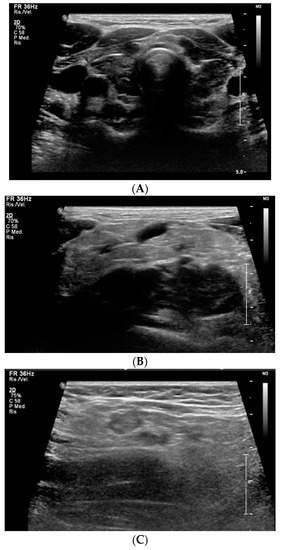

Considering the extreme elevation of TSH, according to the internal protocol, hypothalamic-pituitary magnetic resonance imaging (MRI) was performed and revealed pituitary hyperplasia (diameters of 16 × 12 × 16 mm, with convex upper margin) (Figure 3).

An ophthalmological examination ruled out optic chiasm involvement, describing the visual field as normal.

During hospitalization, the patient’s clinical status showed progressive improvement, the edema regressed and the pericardial effusion decreased to 4 mm. At discharge, after 2 weeks, FT4 levels had increased (6.3 pg/mL), while TSH levels (610.9 μ IU/mL) and creatinine (0.99 mg/dL) had decreased. Levothyroxine dose at discharge was 75 mcg and 100 mcg every other day. 3 weeks after diagnosis, FT4 was in range (11.1 pg/mL). After 2 months, TSH (1.02 μ IU/mL) and creatinine (0.61 mg/dL) also normalized, and prolactin levels decreased significantly (36.2 ng/mL). MRI at 6 months showed resolution of the pituitary hyperplasia, with height reduced from 16 to 3.5 mm. Growth assessment revealed high growth velocity at 6 months (11.6 cm/year) and in the first year of treatment (14.6 cm/year).

In our patient, MRI, performed in accordance with the Center’s internal protocol for patients with very high TSH levels, detected a pituitary hyperplasia. The true incidence of this condition remains largely unknown because MRI is not routinely indicated in the diagnostic pathway of primary hypothyroidism, and it may remain radiologically undocumented. The pathogenesis of pituitary hyperplasia in severe long-standing primary hypothyroidism is explained by the reduction of circulating thyroid hormones. It leads to loss of the negative feedback on hypothalamus, with consequent excessive secretion of thyrotropin-releasing hormone (TRH) and proliferation of thyrotropic cells, leading to compensatory hyperplasia [12]. Enlargement of the pituitary gland in these patients can be very pronounced, even with suprasellar extension; however, unlike pituitary tumors or craniopharyngioma, it rarely causes signs or symptoms. Instead, it regresses with levothyroxine treatment and usually does not require surgery [12].

Figure 3. MRI of pituitary hyperplasia.